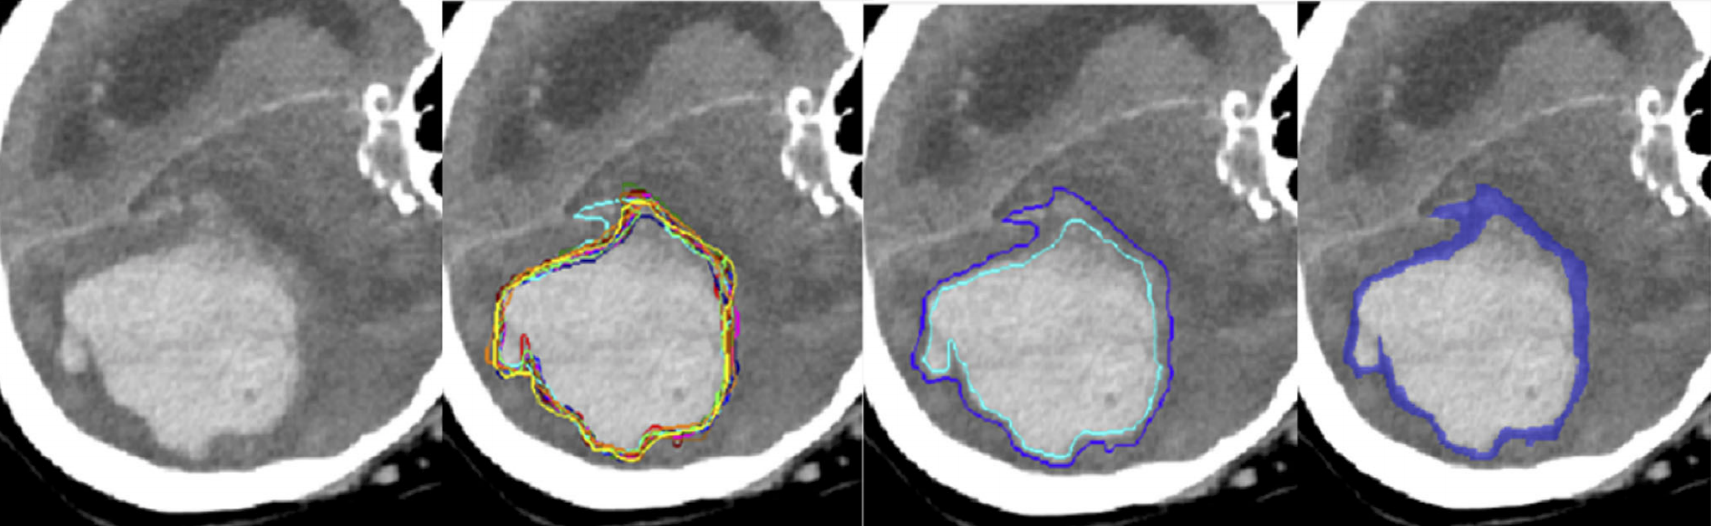

The QUBIQ challenge deals with benchmarking algorithms that quantify uncertainties in biomedical image segmentation. Participants will work on binary segmentation tasks, all of which with multiple annotations from domain experts. To be segmented are various pathologies and anatomical structures, such as brain, kidney, or prostate, in MR or CT image data. A successful algorithm will segment these structures and reproduce the distribution of the experts’ annotations.